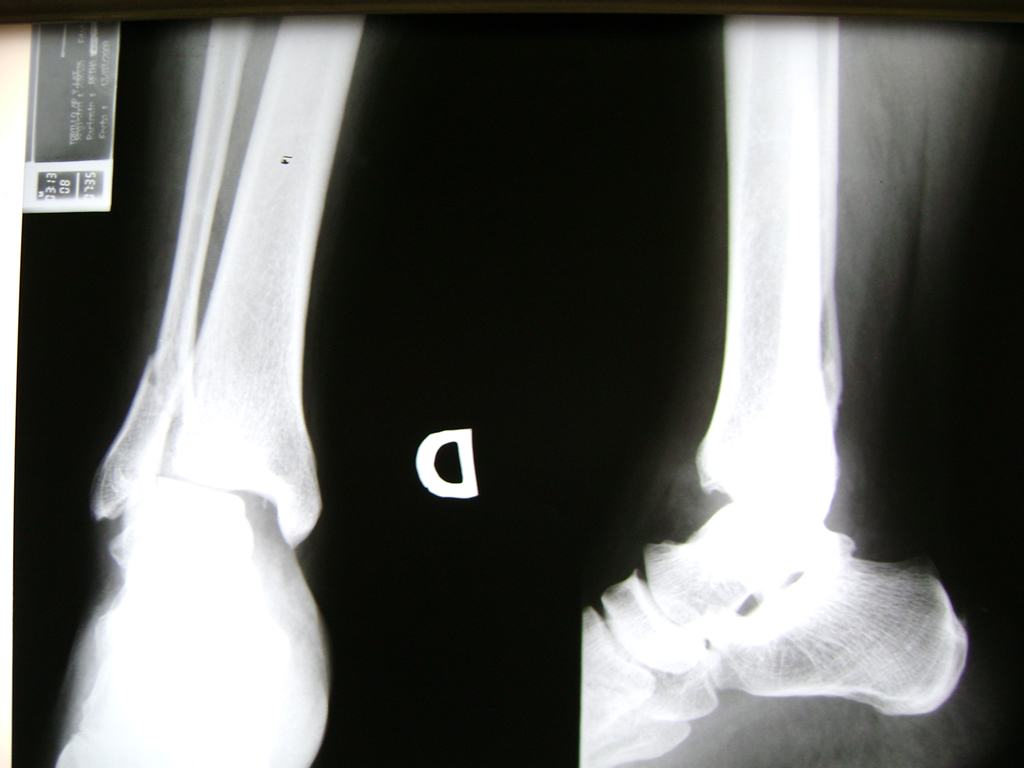

Una fractura de tobillo es la rotura de uno o más de los huesos del tobillo. Estas fracturas pueden ser:

Algunas fracturas de tobillo pueden requerir cirugía si:

- Los extremos de los huesos están desalineados entre sí (desplazados).

- La fractura se extiende hasta la articulación del tobillo (fractura intra-articular).

Cuando se necesita cirugía, es probable que esta implique el uso de clavijas de metal, tornillos o placas para sostener los huesos en su lugar mientras la fractura se consolida. Los elementos de soporte pueden ser temporales o permanentes.